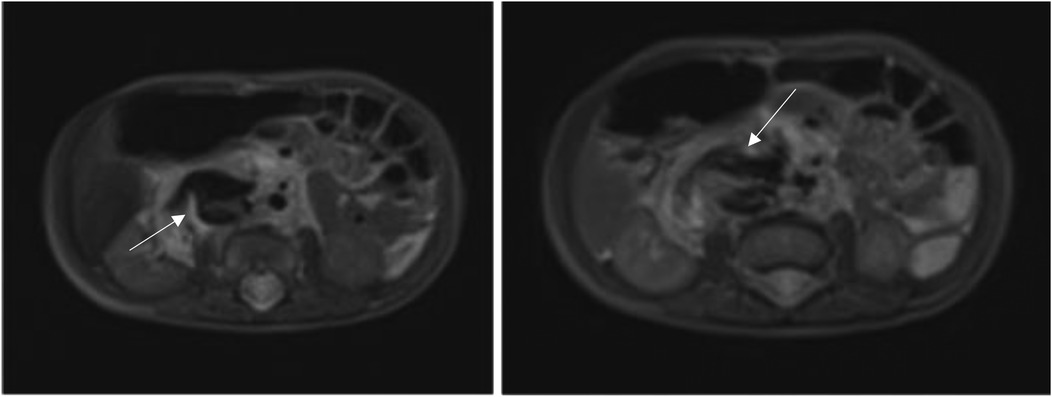

In order to better evaluate the vascularity and vessel proximity of the lesion, our oncologists suggested an abdominal MRI. An intralesional arteriovenous shunt was found in conjunction with a significant IVC dilatation brought on by hyperinflow (Figures 1, 2).

Two MRI scans of the abdominal region, side by side. The left image shows a highlighted area with an arrow, indicating a specific point of interest. The right image also has an arrow pointing to a different area, suggesting another focus point for examination.

Figure 2. Intralesional arteriovenous shunt on axial section at MRI.